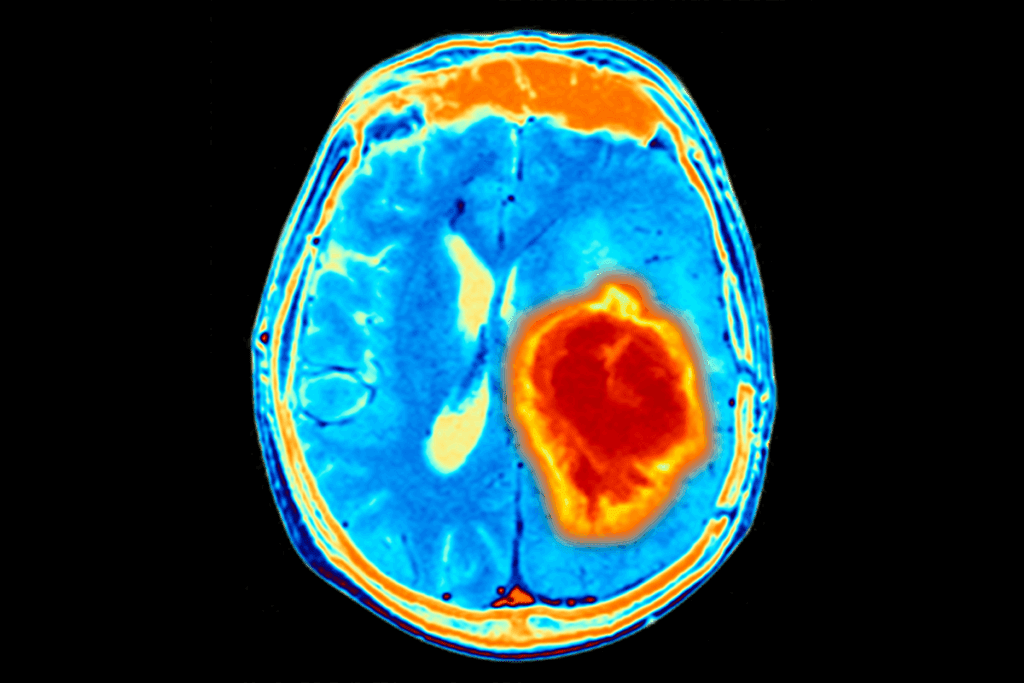

Slow-Growing vs. Aggressive Tumors

Brain tumors in kids can be slow-growing or aggressive. Slow-growing tumors are usually not harmful and might not show symptoms for a long time. On the other hand, aggressive tumors grow fast and can cause symptoms quickly, sometimes in just weeks or months.

Signs of slow-growing tumors can be hard to spot. A child might have headaches or slight mood changes. These could be mistaken for other common issues.

Average Detection Timeframes by Tumor Type

How long it takes to find a tumor varies by type. For example:

- Pilocytic astrocytomas, a slow-growing tumor, might not be found for a long time because they grow slowly.

- Medulloblastomas, being aggressive, are often found sooner because they grow fast and cause severe symptoms.